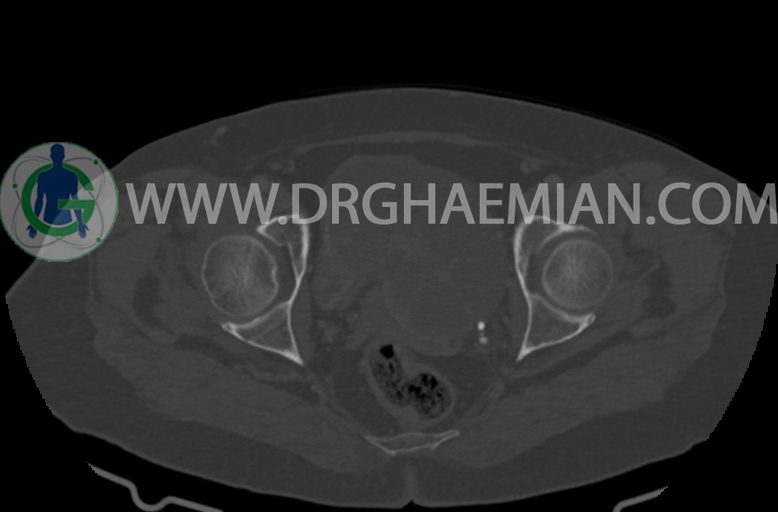

–ضایعه ی mass like هیپردنس- هتروژن به قطر 42mm در سمت راست لگن